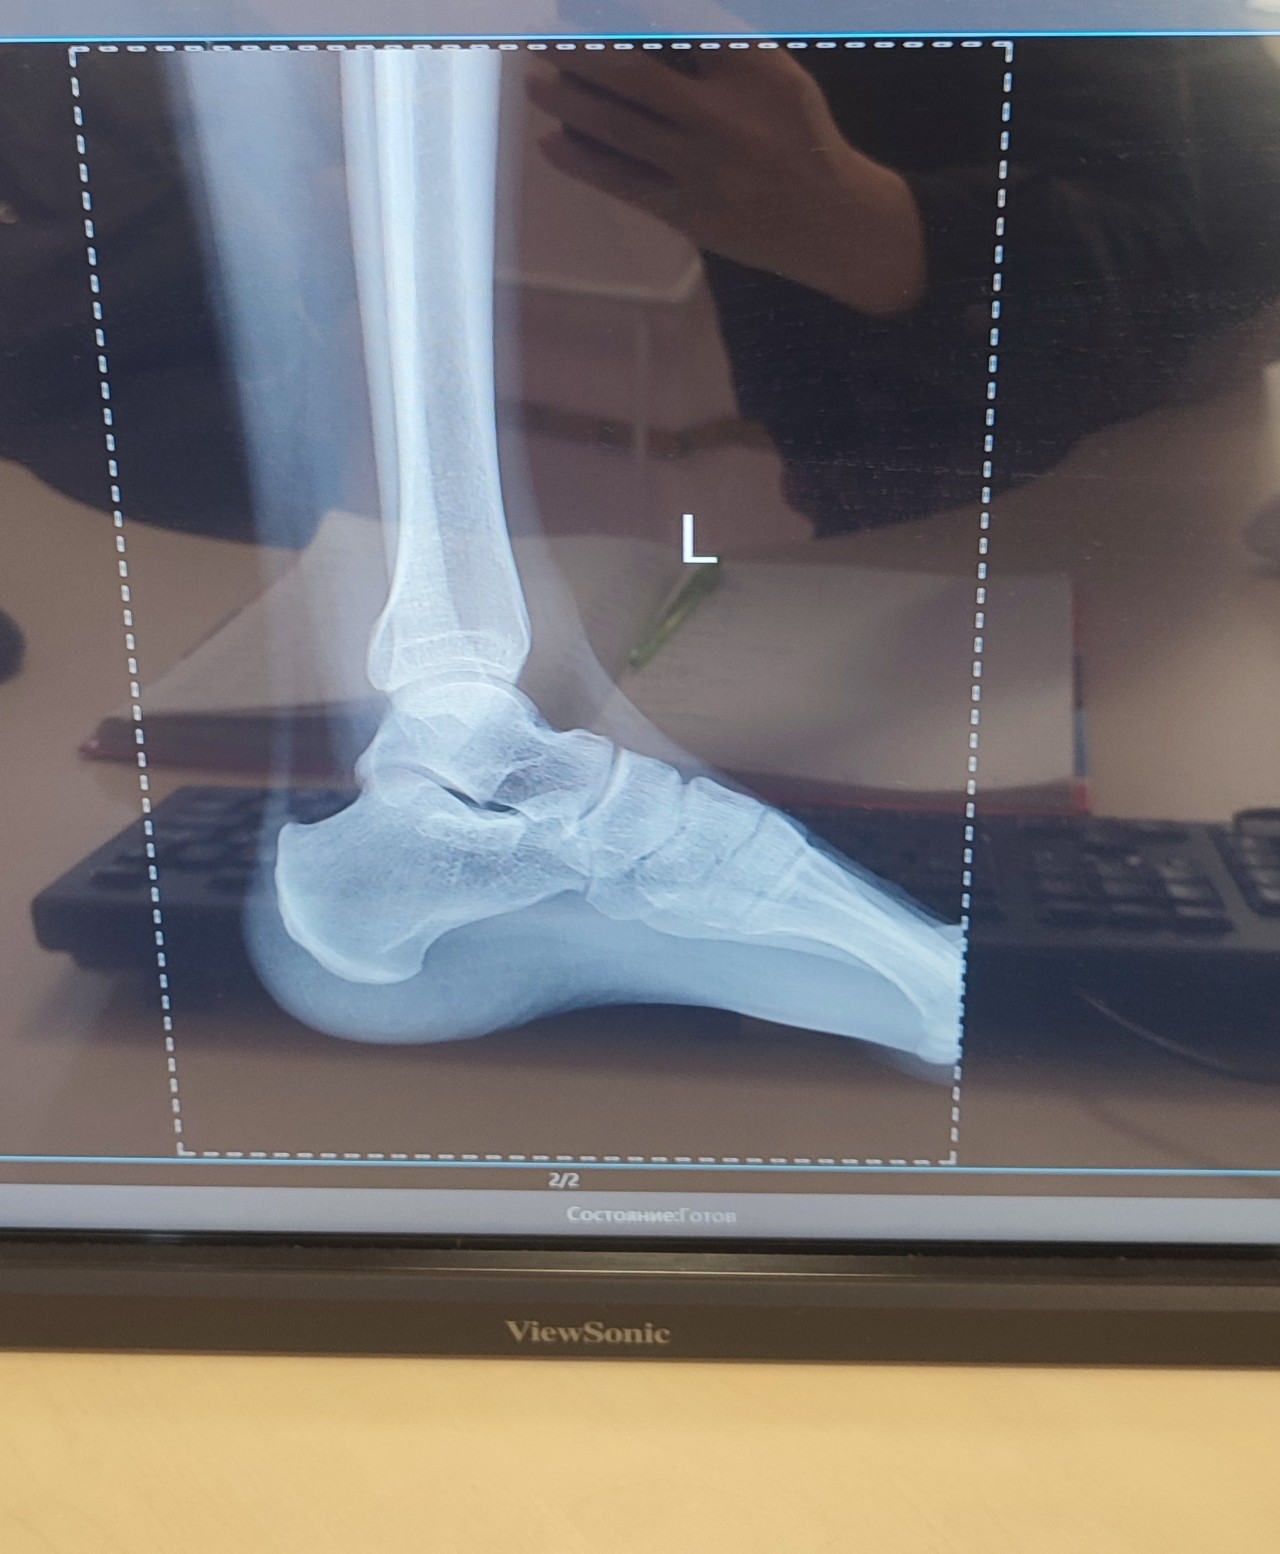

Заключение у ортопеда: S-образный сколиоз фиксированный вправо-2 степени; плоскостопие.